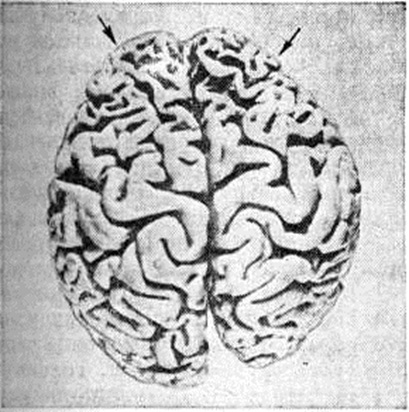

Гистологически отмечаются прогрессирующие хронический дистрофические изменения нервных клеток в виде сморщивания, атрофии, липофусциновой дегенерации, заканчивающиеся цитолизом (смотри полный свод знаний) и приводящие к резкому диффузному, а иногда и очаговому опустошению, которое сопровождается выраженным заместительным глиозом за счёт пролиферации в основном астроцитов и олигодендроглиоцитов (смотри полный свод знаний Глиоз). Клеточное опустошение особенно заметно в верхних слоях (II — III а) коры мозга (рисунок 2). Характерные признаки Пика болезнь — появление набухших баллоновидных клеток с центральным хроматолизом и эктопией ядра (рисунок 3, а), напоминающих нейроны с первичным раздражением при аксональной реакции, иногда превращающиеся в сверх набухшие гомогенизированные клетки, а также появление нейронов с аргентофильными цитоплазматическими шаровидными включениями — тельцами Пика (рисунок 3, б). По данным Эскуролля (R. Escourolle, 1956), набухшие клетки встречаются приблизительно в 60% случаев Пика болезнь, тогда как аргентофильные включения — в 20%. Преимущественная локализация набухших клеток — III — V слои коры, нейронов с аргентофильными включениями — чаще всего гиппокамп. Однако эти изменения могут встречаться во всех образованиях мозга, подвергшихся атрофии, и даже в клетках ствола мозга.

Рис. 2. | ||